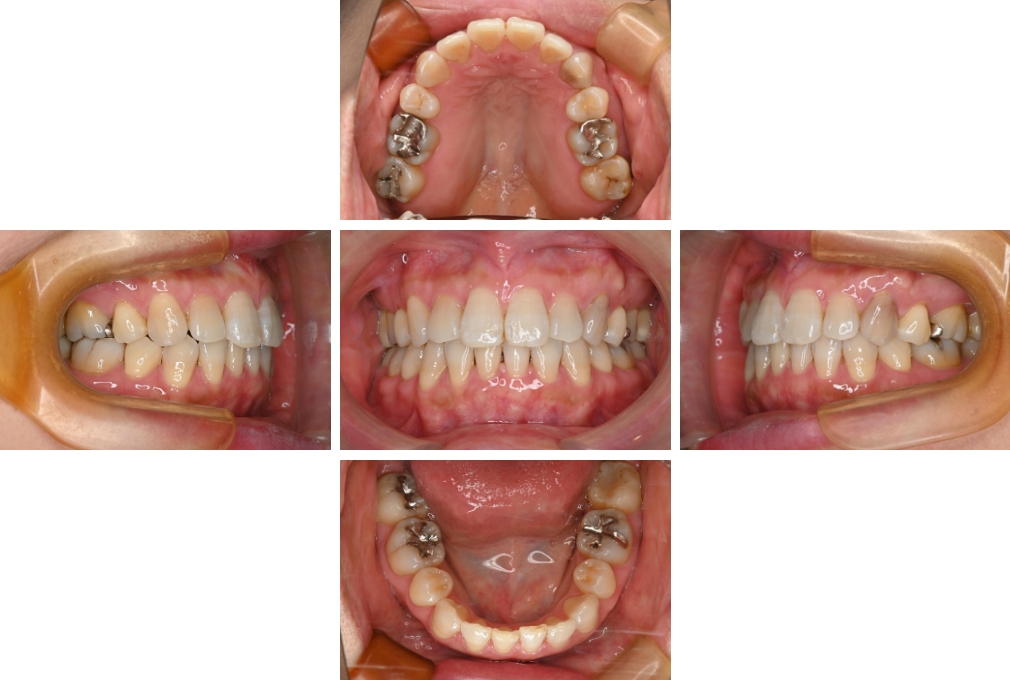

CASE:03

上下顎前突

初診時年齢 18歳4か月

性別 男性

治療費の目安 105万円程度(治療開始時)

歯列の乱れは著しくなく上顎右側側切歯が捻転し口蓋側へ転位していた。また、問診の中で患者さんから最も重視する治療結果として口元の突出の改善の申出があった。下顎が後退した上顎前突傾向ではあったが著しいものではなかった。上下顎前突と診断し上下顎小臼歯抜歯を行っていただき、上下顎舌側マルチブラケット装置を使用して、矯正用アンカースクリューを併用して動的治療を行った。上下顎前歯の後退を十分行い口元の突出感も改善した。治療後10年1か月の来院時には口元の突出感が再発することもなく、下顎前歯の少しの唇舌的なずれはあったが歯列は安定していた。動的治療期間2年2ヵ月間。

治療前

18歳4ヵ月

治療後

動的治療期間2年2カ月間

20歳10か月

10年経過

動的治療終了後10年1カ月

30歳11か月